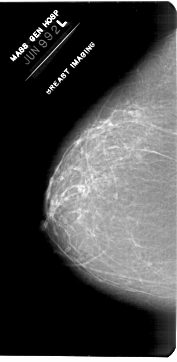

A_1953_1.LEFT_MLO

LEFT_CC LINES 6871 PIXELS_PER_LINE 3361 BITS_PER_PIXEL 12 RESOLUTION 43.5 NON_OVERLAY

LEFT_MLO LINES 6871 PIXELS_PER_LINE 3526 BITS_PER_PIXEL 12 RESOLUTION 43.5 NON_OVERLAY